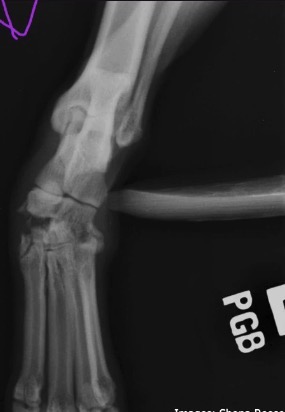

What view is this, what is being seen, what aspect of the joint is seen?

stress radiography on DP view

Opens up medial side of joint, medial intertarsal joint indicates trauma on medial side

Fracture fragments can be seen that are not seen when the joint is not opened up